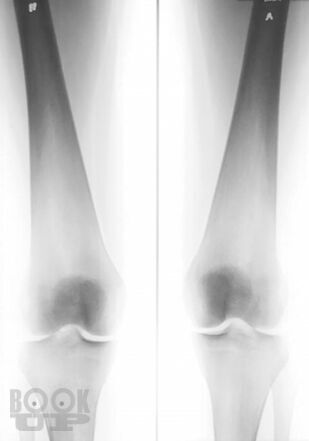

Болезнь Гоше относится к системным заболеваниям неопухолевой природы, в основе которых лежат наследственные дефекты метаболизма, приводящие к накоплению в органах и тканях нерасщепленных продуктов нормального обмена веществ. В случае болезни Гоше дефектом метаболизма является дефицит фермента, ответственного за метаболизм липидов.

Цель книги — познакомить врачей различных специальностей с основными клиническими проявлениями болезни Гоше, продемонстрировать исключительную вариабельность течения болезни на примере конкретных клинических случаев, показать характерные ошибки диагностики и ведения пациентов с болезнью Гоше. Помимо врачей, книга может быть полезной для образования самих пациентов и их родственников, так как некоторые особенности клинического течения заболевания напрямую связаны с социально-бытовыми аспектами: образом жизни, физической активностью, наличием бытовых интоксикаций и др.